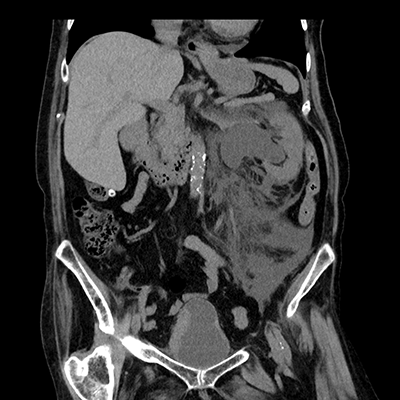

臨床画像例

中山氏 IPVは被ばく低減に役立っています。

当院では、体幹部は平均的にガイドライン*2比で50%近く低被ばくの条件で撮影していますが、読影の先生にも問題なく診断して頂いています。低被ばくに撮影することは、患者さんのメリットに繋がります。当院では、さらに患者さんに安心していただくため、被ばく線量を集計して患者さん向けの説明ツールを作っています。